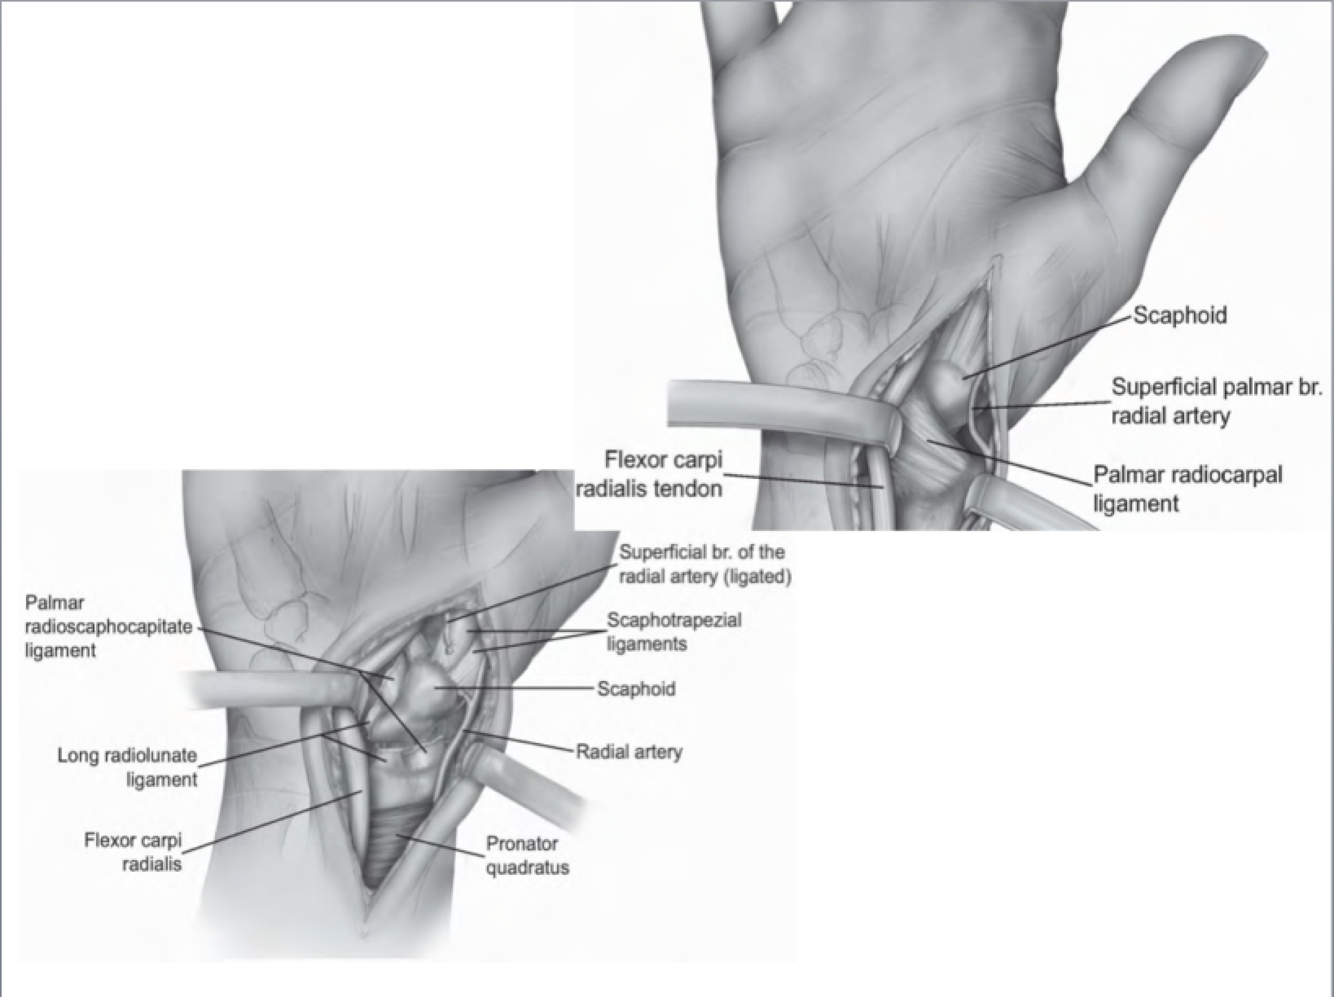

Russe Approach (Volar Approach to Scaphoid)

Interval: Radial a. and FCR (Median N.)

Approach:

- Incision centred over the scaphoid tubercle

- Identify FCR tendon, then cut through subsheath like in FCR.

- Split thenar muscles distally

- Incise capsule over scaphoid and expose scaphoid up to ST joint

Dangers: Radial A.